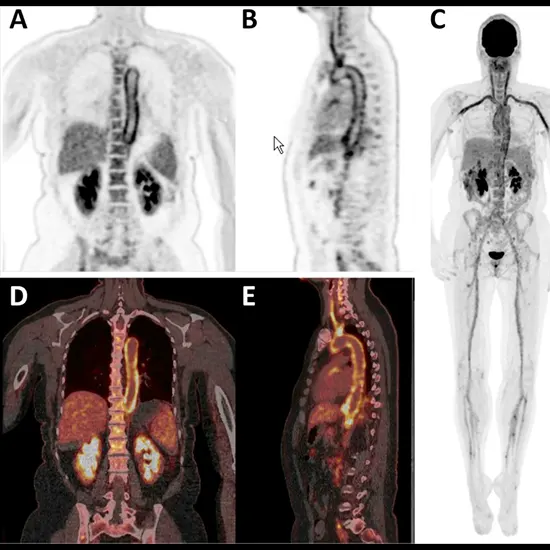

PET-CT (Positron Emission Tomography-Computed Tomography) may be a therapeutic imaging procedure that combines two sorts of looks to create point by point pictures of the interior of the body.

PET-CT can be valuable in such cases because it can offer assistance recognize regions of inflammation or disease within the body which will be causing the fever.

The CT component of the filter gives point by point anatomical data that can offer assistance localize ranges of expanded tracer uptake detected by the PET filter. This data can be utilized to direct assist demonstrative testing or to target particular zones for biopsy.

In rundown, PET-CT could be a valuable imaging method within the assessment of patients with pyrexia of obscure origin, because it can offer assistance recognize ranges of inflammation or disease that will be causing the fever.